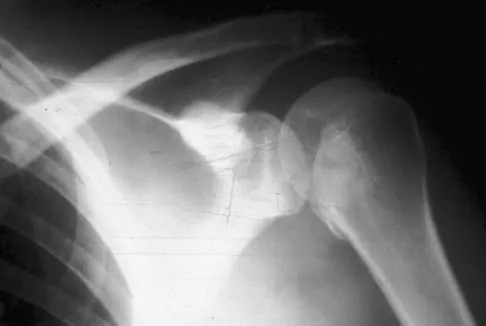

A 70-year-old man who underwent an uncomplicated large rotator cuff repair 6 months ago is now seeking a second opinion regarding persistent pain and weakness in his shoulder. Examination reveals that his incision is well healed and unreactive. The surgical report suggests that the tendons were secured back to bone with sutures through the greater tuberosity. Figure 28 shows a radiograph that was obtained 1 week ago. What is the most likely diagnosis?

Symptoms can persist following a rotator cuff repair for a variety of reasons. In the early postoperative period, infection is the primary concern. Stiffness and loss of motion can occur because of postoperative scarring. Complex regional pain syndrome can occur but is rare, and the diagnosis is not made with a plain radiograph. This radiograph shows a superiorly migrated humeral head that articulates with the acromion, indicating that the repair has failed. While large to massive tears may fail more commonly than once thought, the clinical outcome may be satisfactory in many patients. Mansat P, Cofield RH, Kersten TE, Rowland CM: Complications of rotator cuff repair. Orthop Clin North Am 1997;28:205-213.